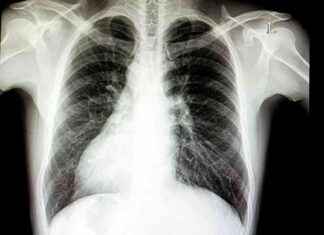

Understanding Situs Inversus: Organs on the 'Wrong' Side Situs inversus is a rare genetic condition that affects approximately 1 in 10,000 people, with men being 1.5 times more likely than women to experience this unique...